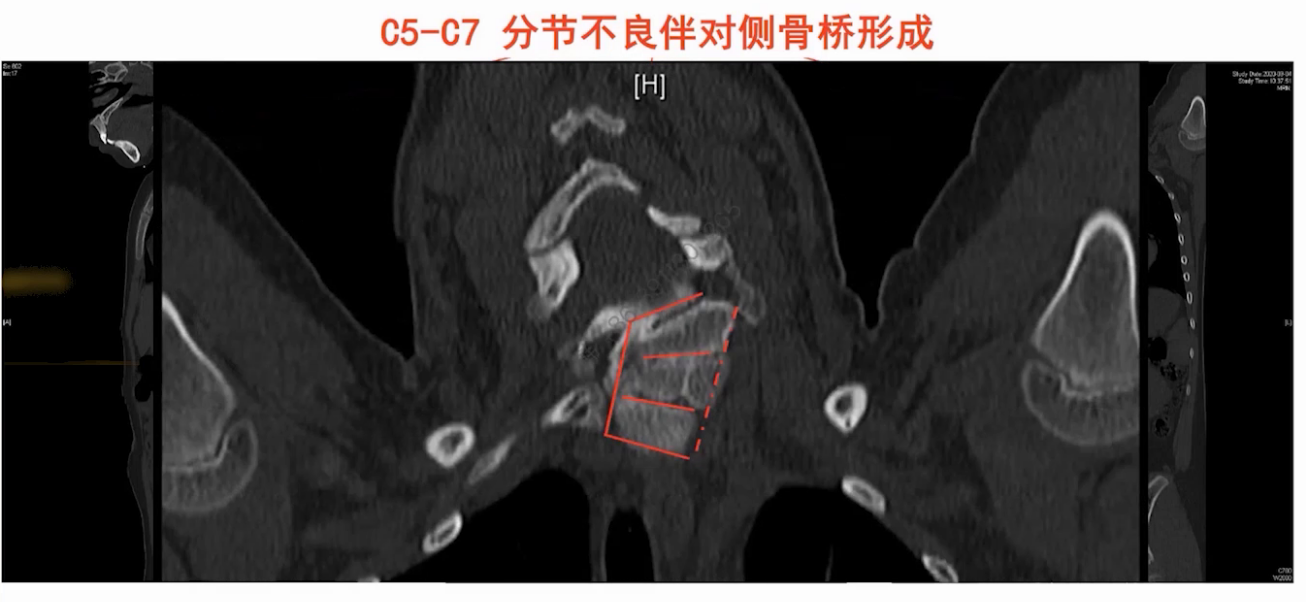

CT显示C5-C7椎体分界不清,伴对侧骨桥形成。三维重建更清晰展示局部畸形结构。